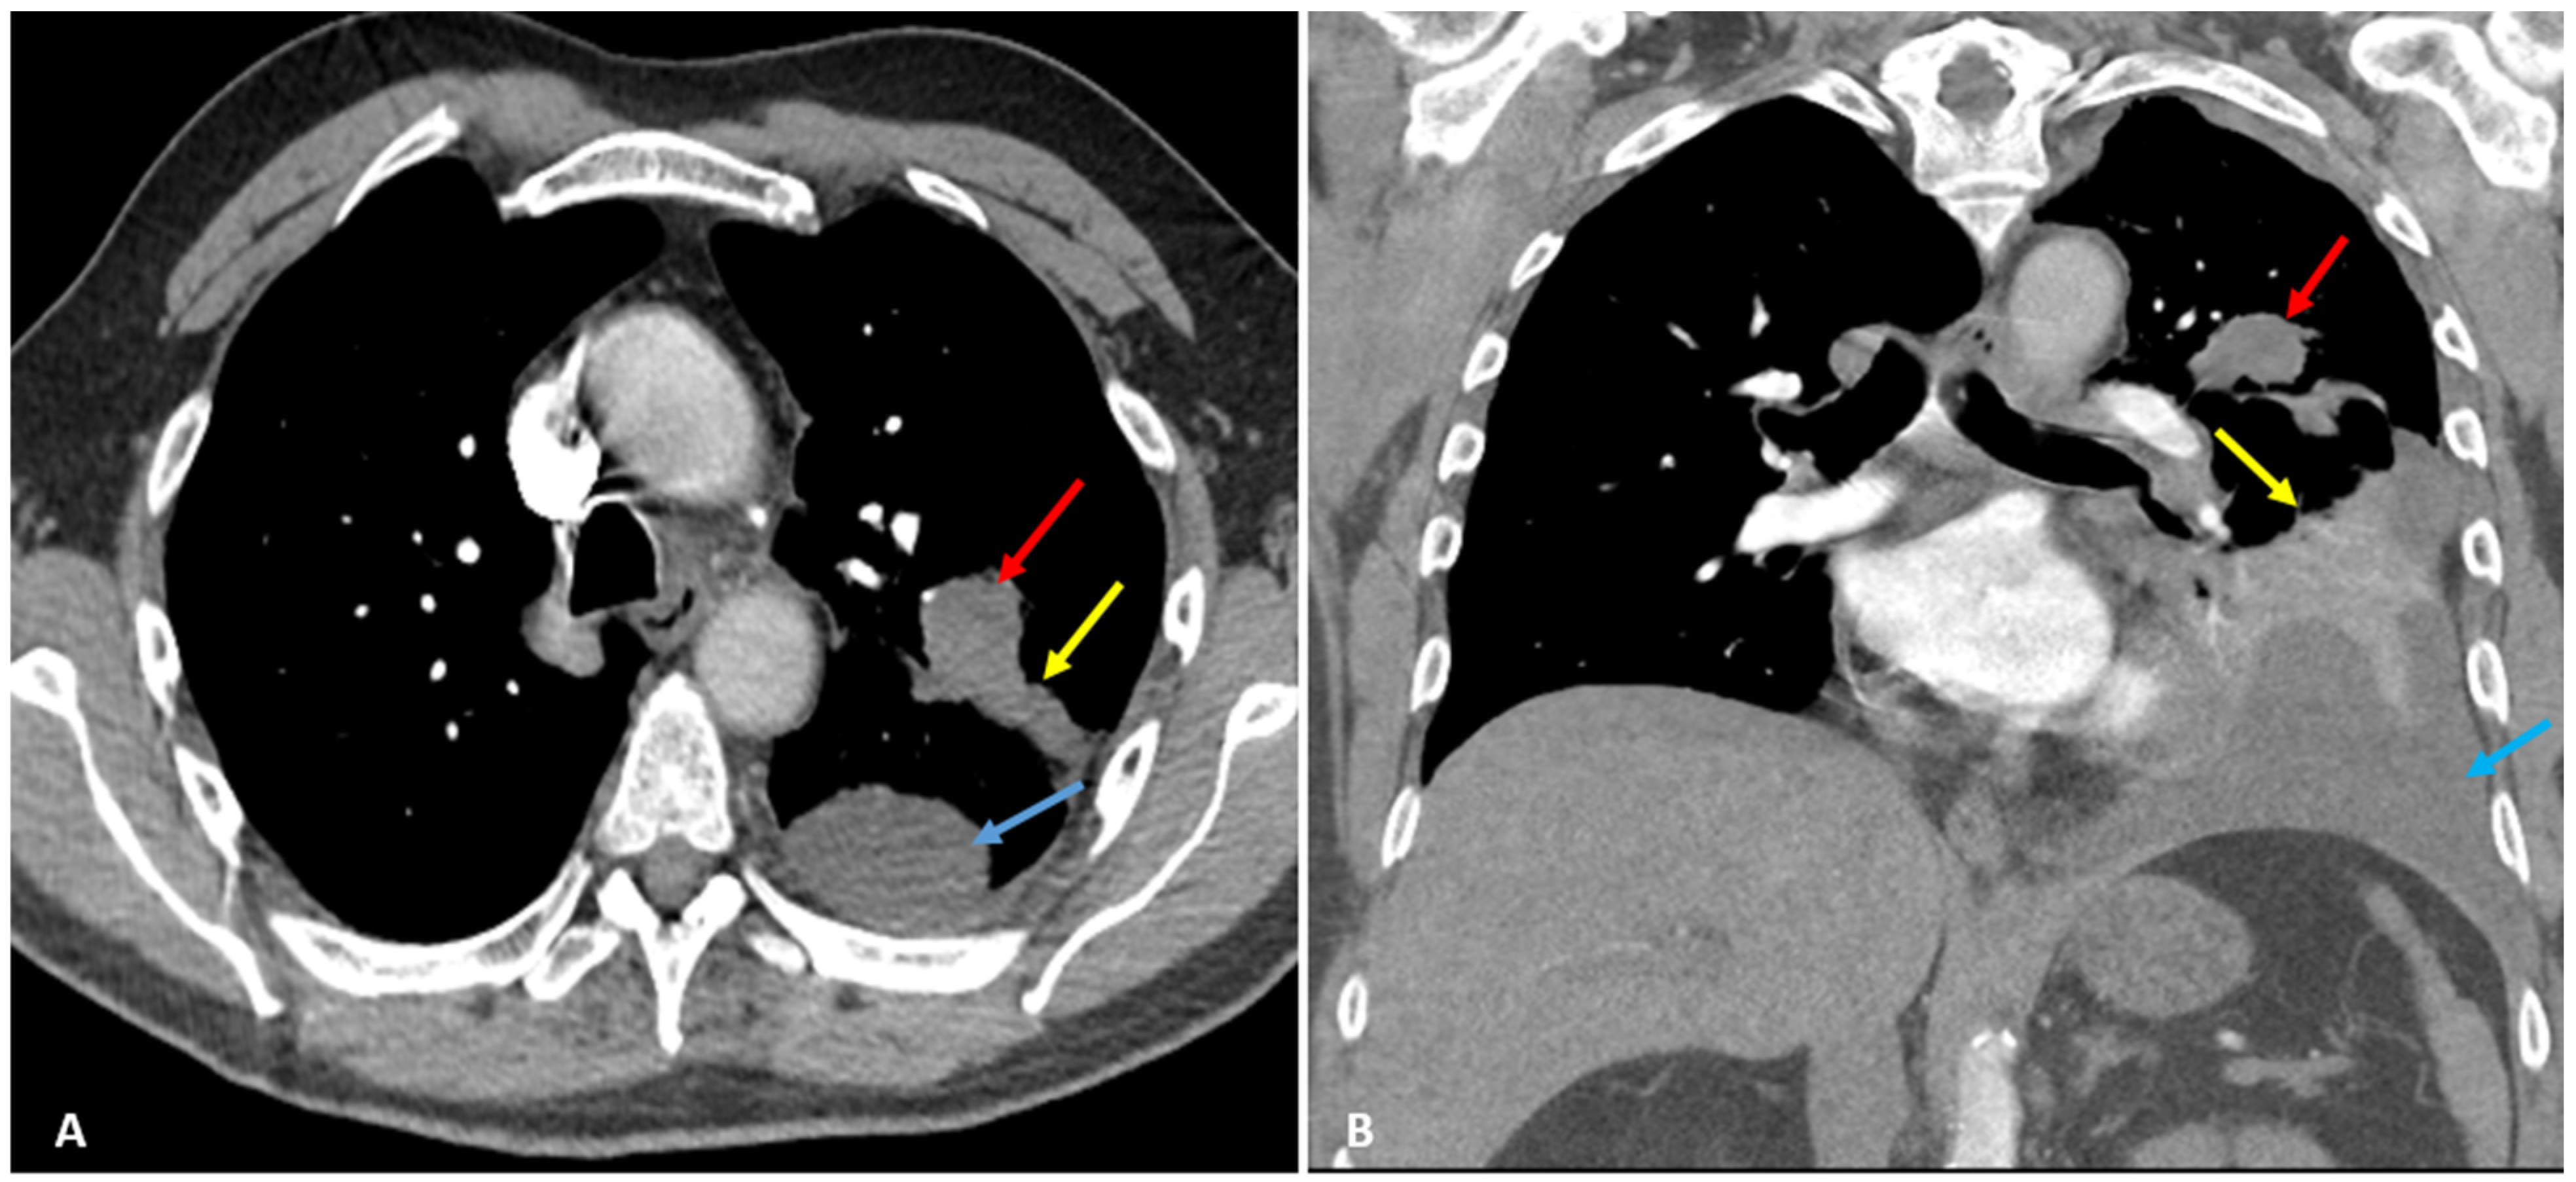

Later, he started to experience excruciating left lateral chest pain, radiating to his shoulder and neck, 10/10 in intensity, and worsened with deep inspiration, leading to shallow breathing and dyspnea. He returned to his primary physician, who ordered a chest X-ray (CXR) and computed tomography (CT) chest with intravenous (IV) contrast revealing left upper lobe peri-bronchial mass (red arrows) measuring 3 × 2 cm in diameter, distal obstructive atelectasis, and left pleural effusion (Figure 1).

Figure 1.

Axial (A) and coronal (B) CT scan with IV contrast shows left upper lobe peri-bronchial mass (red arrows) measuring approximately 3 × 2 cm in diameter. Distal obstructive atelectasis (yellow arrows) and left pleural effusion (blue arrows) are observed as well.